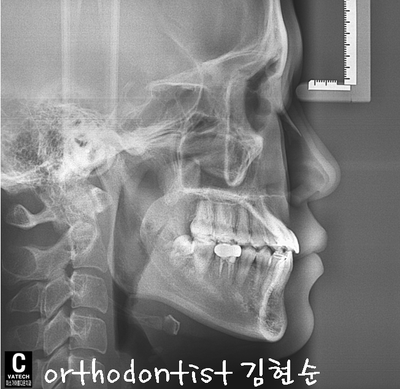

( 김 현순 대표 원장님 )

- 치아 중심선도 개선되었습니다

- 위에 처음과 비교했을 때 많이 개선된 모습을 볼 수 있습니다

- E - LINE에서도 돌출 턱이 들어간 모습을 처음과 비교할 수 있습니다